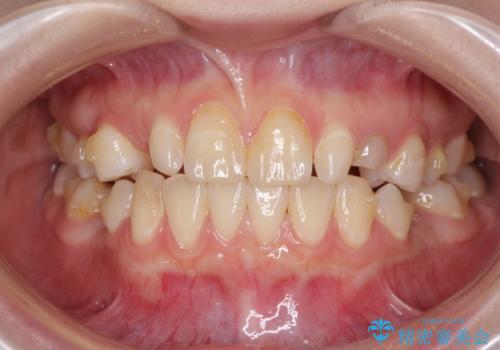

欠損と残存乳歯 矯正治療とインプラント治療

- 残存した乳歯や歯の欠損、歯並びを気にして来院された患者様です。

乳歯を残した状態は予後がよくないこと、矯正治療と補綴治療を総合的に進めていきたいとのことで、インビザラインによる矯正治療とインプラント補綴治療を並行して進めていくこととしました。